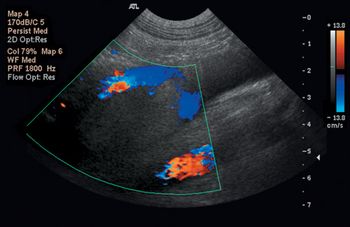

Thrombosis is a complication of many diseases in veterinary medicine.